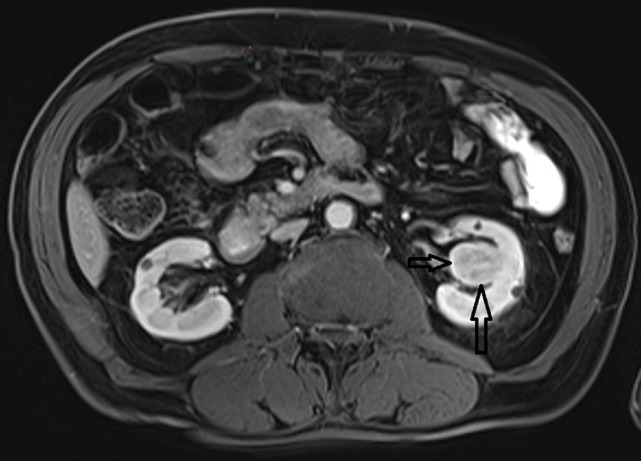

肾脏的功能受到其他器官疾病的影响。在这里,我们提出了一个肾功能正常的老年透析前患者,尽管有许多合并症,但肾脏学随访10年。患者男性,75岁,高血压病史15年,吸烟60包年,诊断为肌肉浸润性膀胱癌(MIBC)和左肾同步中央定位透明细胞肾细胞癌(ccRCC)。入院时患者估计肾小球滤过率(Glomerular Filtration Rate, eGFR) (CKD-EPI-cre)为54mL/min/1.73m2,左肾切除术后患者的eGFR降至35ml /min/1.73m2。经过10年的随访,患者的右肾功能正常,eGFR为24 mL/min/1.73m2,尽管进行了根治性膀胱切除术并尿路转移、根治性肾切除术、重度吸烟、心肾综合征、慢性阻塞性肺疾病和高血压。众所周知,高血压、吸烟、癌症、感染、肺病和心脏病等合并症会造成不可逆的肾脏损害,并会导致肾功能下降。这些合并症的适当和早期诊断和治疗可以使肾脏健康老化,而不需要透析。

Kidneys are functionally affected by the diseases of other organs. Here, we present an elderly predialysis patient with a functioning kidney for 10 years of nephrological follow-up despite many comorbidities. A 75-year-old male patient with a medical history of hypertension for 15 years and 60 pack years of cigarette smoking, was diagnosed as muscle invasive bladder cancer (MIBC) and synchronous centrally located clear cell renal cell carcinoma (ccRCC) in the left kidney. At admission, the patient had an Estimated Glomerular Filtration Rate (eGFR) (CKD-EPI-cre) of 54mL/min/1.73m2, after left nephrectomy eGFR of the patient decreased to 35 mL/min/1.73m2. After ten years of follow-up, the patient's right kidney had been functional with a eGFR of 24 mL/min/1.73m2 despite radical cystectomy with urinary diversion, radical nephrectomy, heavy smoking, [cardiorenal syndrome, chronic obstructive pulmonary disease, and hypertension. It is well known that comorbidities such as hypertension, smoking, cancers, infections, pulmonary and heart diseases contribute to irreversible kidney damage and are additive to decreasing kidney function. Appropriate and early diagnosis and treatment of these comorbidities permit healthy aging of the kidneys without the need for dialysis.